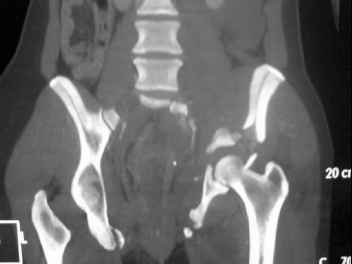

I'm posting this case on behalf of Dr. Pedro Caba, he is unable to post but able to read. 41 yo female , fall from 10 meters five days ago. Hemodynamically unstable on admission treated by angio and embolization and skeletal traction, with no external support. No associated injuries. Based on CT scan the pt has a both column fracture with conminuted dome and displaced anterior column and a sacral Denis 1 fracture with a displaced left ala. I think the best approach for the acetabular fracture is ilioinguinal with Smith-Petersen extension but don't know exactly the sequence . Will you start with the sacral fracture? Which technique? Thanks in advance Pedro Caba Unidad de Trauma Hospital 12 de Octubre Madrid Spain

This patient has extensive and complicated skeletal injuries...much more data (such as additional relevant images and clinical information regarding the soft tissues and overall patient status) would help us formulate an informed plan.

The sacral pattern alone is quite difficult and seems to be some version of an H-pattern, but I can’t tell from these films.

General condition is fine except for an intractable pelvic pain, no associated injuries (only ankle fracture), no sciatic nerve injury.

The soft tissues are also in mild condition, buttock hematoma and probably a Morel-Lavalle. I send some more CT images. There are some conminution in the posterior column (I don’t have images now). The patient is scheduled for surgery next Monday. The plan is percutaneous sacral fixation and then ilioinguinal approach .

This complex and displaced sacral injury is likely an H pattern...2 hemipelvic components, an upper sacral component which remains attached to the lumbar spine, and a caudal sacral component...there are typically anterior ring injuries as well...in this patient's example, the left sided acetabulum also has been exploded.

The hemipelvic components' displacements depend on their instability...this patient's left side seems to be the worst.